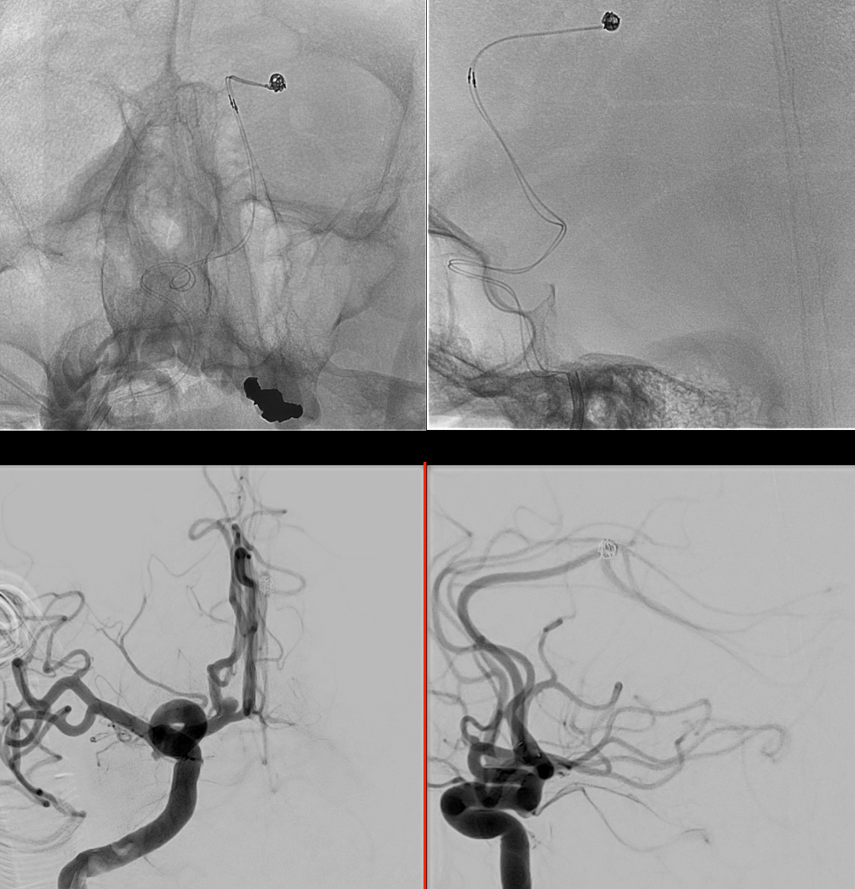

During Embo

Before detaching the Artisse. Same acquisition protocol as before Artisse positioning; bilateral 50% contrast (300 mg/ml) manual injection; followed by 50% FOV 5123 matrix. Note the artifacts caused by the radiopaque markers and pusher of the Artisse.

Post